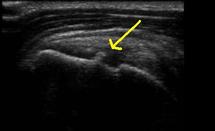

• Type 1 : formation échogène avec cône d’ombre pur

• Type 2 : formation échogène avec cône d’ombre impur (partiellement atténuant)

• Type 3 : formation échogène sans cône d’ombre

• Type 4 : formation échogène avec zone centrale hypoéchogène.

On comprend aisément que les types 1 et 2 correspondent aux calcifications dures, le type 3 aux calcifications molles, et le type 4 aux calcifications en cours de liquéfaction.